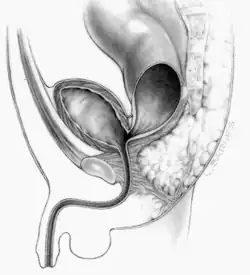

Peña und deVries verfeinerten die obigen Methoden und beschrieben das Verfahren als posteriore sagittale Anorektoplastik.[16] Derzeit ist es das Standardverfahren zur Behandlung der Fehlbildung. Die Operation erfolgt in Bauchlage. Der Schließmuskel wird einer Elektrostimulation unterzogen, um die vorhandene Kraft für die Kontraktion zu bestimmen. Diese Bestimmung kann als Indikator für spätere Kontinenz des Patienten benutzt werden. Im Gegensatz zum obigen Verfahren erfolgt die Schnittführung genau in der Mittellinie. Peña-deVries konnten hierdurch eine günstigere Prognose für Stuhlkontinenz nachweisen. Danach trennt der Operateur das Rektum vom Urogenitaltrakt, bis ausreichend Länge vorhanden ist, um es am Perineum zu anastomieren. Der Durchmesser des Anus ist nach der Operation zunächst kleiner, als für das Alter üblich wäre, und muss geweitet werden. Mit Hegarstiften unterschiedlicher Größe kann das Gewebe bis zur notwendigen Größe gedehnt werden. Dadurch bleibt die muskuläre Spannung zur Gewährleistung der Kontinenz erhalten.